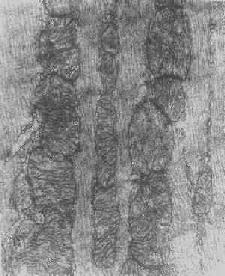

线粒体内晶形包含体(进行性肌营养不良症)

图1-12 线粒体内晶形包含体(进行性肌营养不良症)